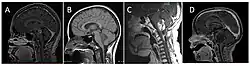

Neuroimaging, such as MRI, is the main diagnostic tool for brain stem gliomas. In very rare cases, surgery and biopsy are performed.